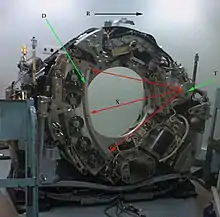

T: X-ray tube

D: X-ray detectors

X: X-ray beam

R: Gantry rotation

X-ray computed tomography operates by using an X-ray generator that rotates around the object; X-ray detectors are positioned on the opposite side of the circle from the X-ray source.

In conventional CT machines, an X-ray tube and detector are physically rotated behind a circular shroud (see the image above right). An alternative, short lived design, known as electron beam tomography (EBT), used electromagnetic deflection of an electron beam within a very large conical X-ray tube and a stationary array of detectors to achieve very high temporal resolution, for imaging of rapidly moving structures, for example the coronary arteries. Systems with a very large number of detector rows, such that the z-axis coverage is comparable to the xy-axis coverage are often termed cone beam CT, due to the shape of the X-ray beam (strictly, the beam is pyramidal in shape, rather than conical). Cone-beam CT is commonly found in medical fluoroscopy equipment; by rotating the fluoroscope around the patient, a geometry similar to CT can be obtained, and by treating the 2D X-ray detector in a manner similar to a CT detector with a massive number of rows, it is possible to reconstruct a 3D volume from a single rotation using suitable software.